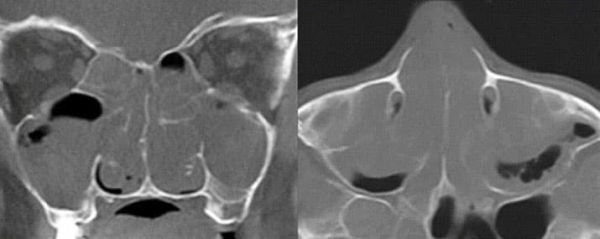

У всех пациентов, которым проводилась КТ околоносовых пазух или рентгенография (34 человека, 65,4 %), были обнаружены изменения в ОНП (см. рисунок). Среди пациентов, которым данные обследования не проводились (18 человек, 34,6 %), 11 человек относились к грудному или раннему преддошкольному возрасту.

Рисунок. Измененные околоносовые пазухи пациента с муковисцидозом. Снимок сделан в 3-й ГДКБ Минска.